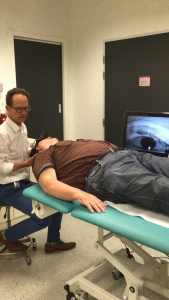

Ruim 12 uur onderweg geweest en 578 kilometers gereden (Leeuwarden-Antwerpen vv) zijn wij (mijn vrouw en ik) blij maar wel moe dat we dit bezoek aan professor dr. Floris Wuyts werkzaam aan het UZA te Antwerpen hebben volbracht. Het heeft mij in ieder geval een nieuwe diagnose opgeleverd nl. Vestibulaire Paroxysmien (VP).Na een intake gesprek met NKO arts Van Haesendonck-Gilles en professor Wuyts, heb ik mijn verzamelde medische gegevens, een gedetailleerde overzicht van de evenwichtsstoornissen vanaf 2012 tot heden en een ingevulde SO STONED formulier ter beschikking gesteld, zodat er een grote hoeveelheid gegevens aanwezig was omtrent mijn ziekteverloop. Vervolgens heb ik nog een uitgebreide gehoortest gedaan en tenslotte kreeg ik een bril op waardoor Floris mijn oog bewegingen kon zien door mij in een verschillende houdingen te plaatsen. Als er een vorm van duizeligheid of misselijk gevoel optreedt is het zichtbaar op het scherm (zie foto’s).

Bij de foto’s: Professor dr. Floris Wuyts onderzoekt mij en kijkt naar de oogbewegingen op het scherm.